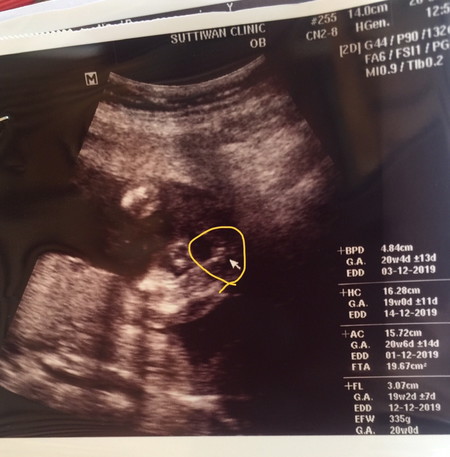

ท้อง5เดือนกว่า

ซาว์ดทั้ง2รอบคุณหมอบอกได้ลูกสาวค่ะ. แม่แอบดีใจมากๆ. คลอดเดือนธันวาคม. แม่ๆบ้านไหนกำหนดคลอดเดือนธันวาบ้างค่ะ ได้ลูกเพศอะไรกัน